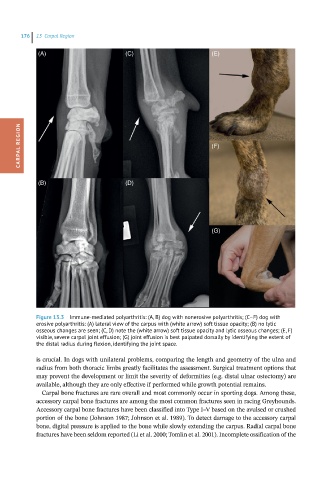

Figure 13.3 Immune-mediated polyarthritis: (A, B) dog with nonerosive polyarthritis; (C–F) dog with

erosive polyarthritis: (A) lateral view of the carpus with (white arrow) soft tissue opacity; (B) no lytic

osseous changes are seen; (C, D) note the (white arrow) soft tissue opacity and lytic osseous changes; (E, F)

visible, severe carpal joint effusion; (G) joint effusion is best palpated dorsally by identifying the extent of

the distal radius during flexion, identifying the joint space.